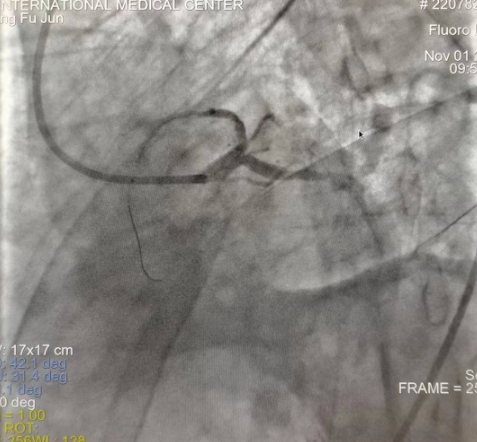

閉塞的血管再通時間取決于急救時長、轉運時長和治療時長,在前兩方面,醫(yī)院已為患者爭取了最短時間?;颊呒覍龠h在陜北,雖然已在趕來的路上,但最快抵達西安也要3小時,在與患者家屬電話溝通同意急診手術后,醫(yī)療總值班代家屬簽字,康曉軍在請示心臟病醫(yī)院王海昌院長及心臟內(nèi)科CCU尚福軍主任后,積極進行術前準備。在沒有家屬陪同、沒有交費、沒有辦入院手續(xù)的情況下,患者經(jīng)胸痛中心綠色通道被送往心臟冠脈介入手術室,打通了完全閉塞的心臟前降支近段血管。